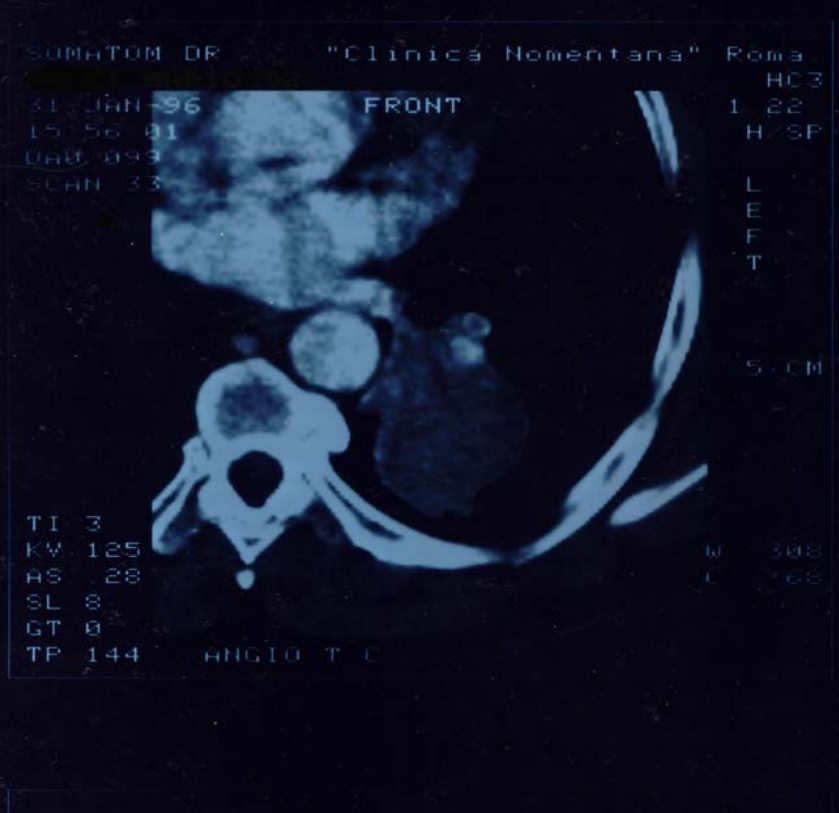

Figure1